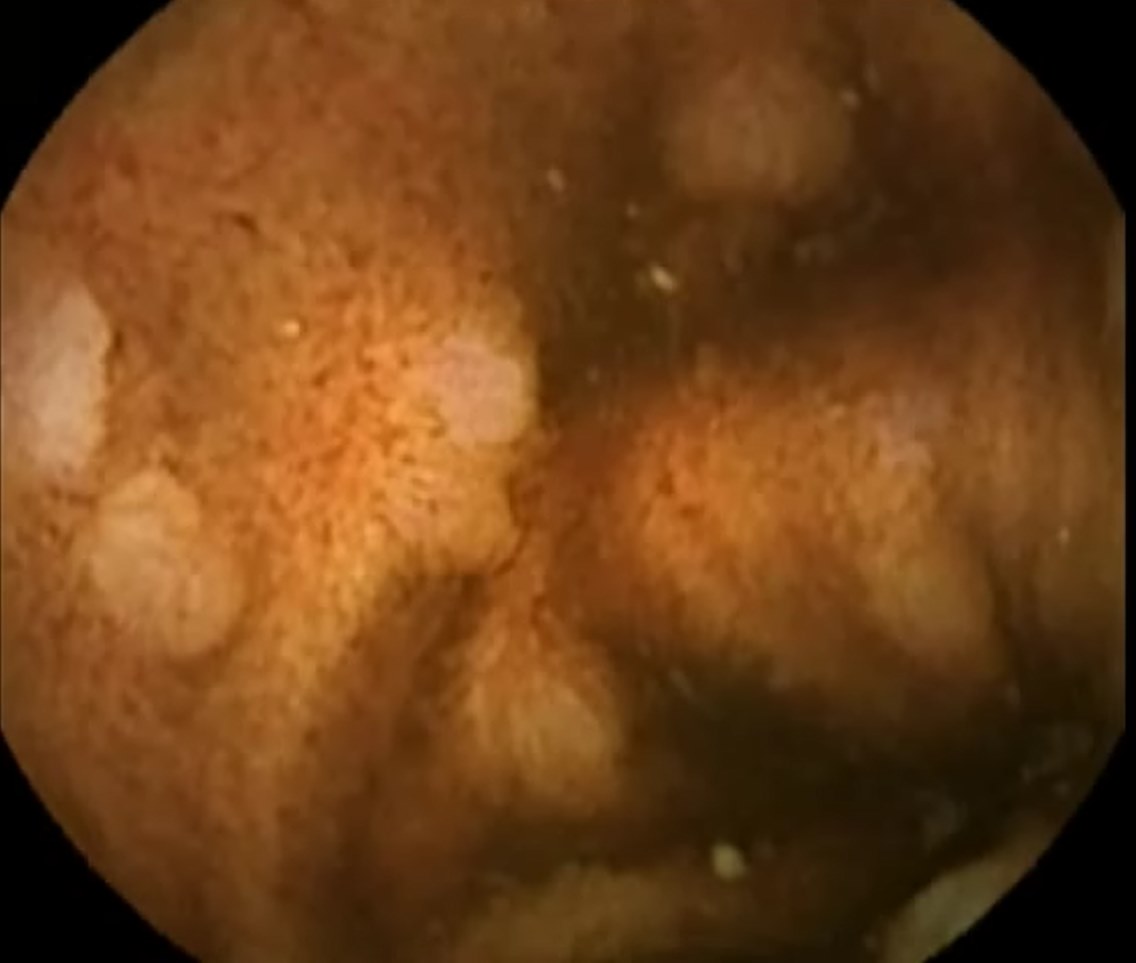

Capsule Endoscopy: Ileum Terminale, Lymphoid Hyperplasia

Capsule Endoscopy: Ileum Terminale, Lymphoid Hyperplasia. Just click on a picture!